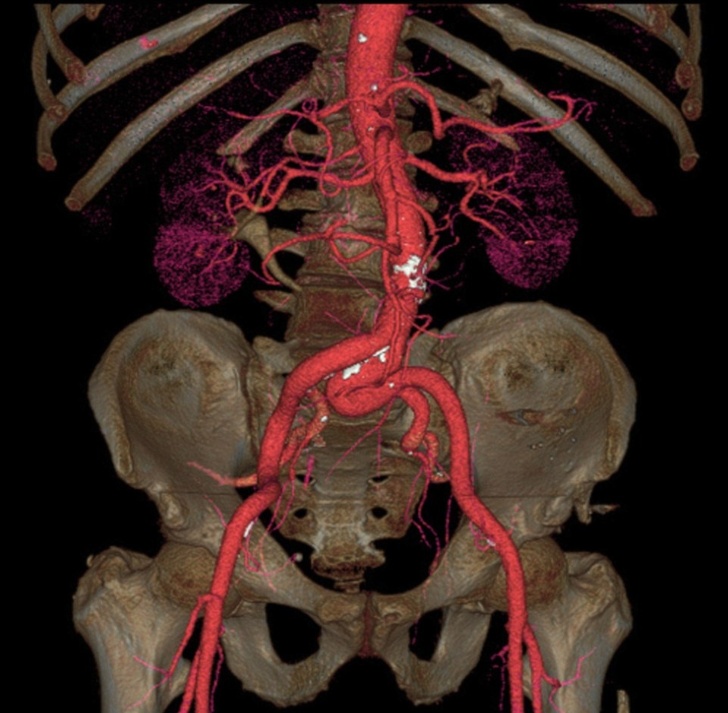

17. Аорта — найбільша артерія нашого тіла